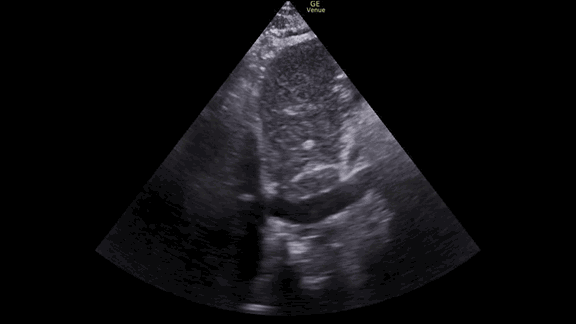

The IVC, on the other hand, did not fit the picture we were expecting. It was not flat. In fact, it showed very little respiratory variation at all.

First we get a parasternal long axis view:

We must be able to identify the structures in the image: